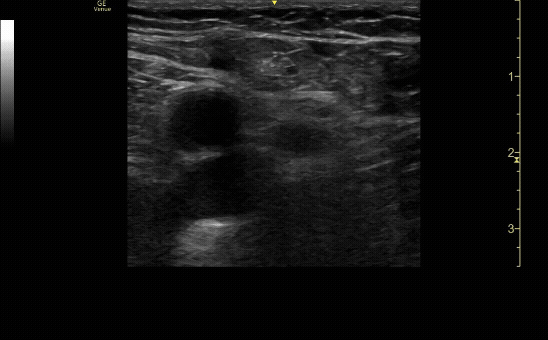

Proximal enlarged lymph node.

c/o Jordyn Cohen, MD